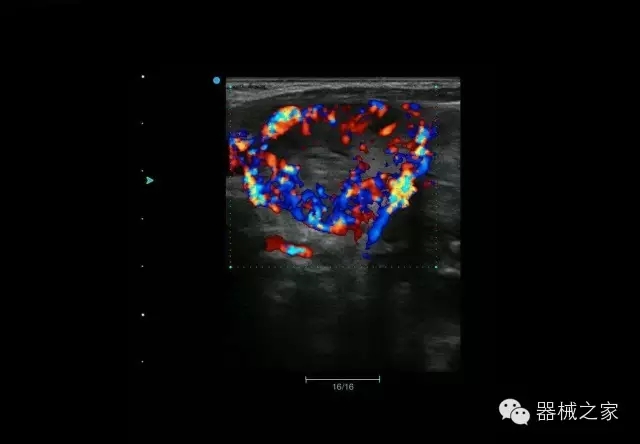

結(jié)甲

腎臟血流

肝血管瘤